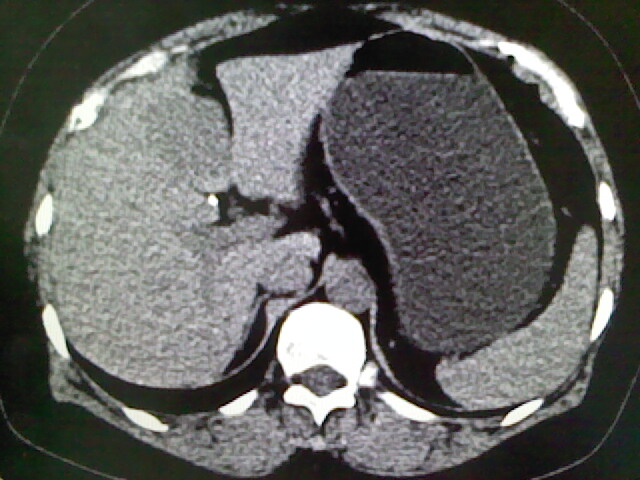

以下是引用卜一在2009-4-2 13:26:00的发言:[br]胆囊颈部结石伴胆囊炎!另:建议增强,待除外肝内占位及胆囊占位!

以下是引用liaoqiang在2009-4-2 16:23:00的发言:[br]胆囊是否切除?胆囊颈区致密影考虑金属夹?结石?肝脏右叶低密度影,考虑增强。